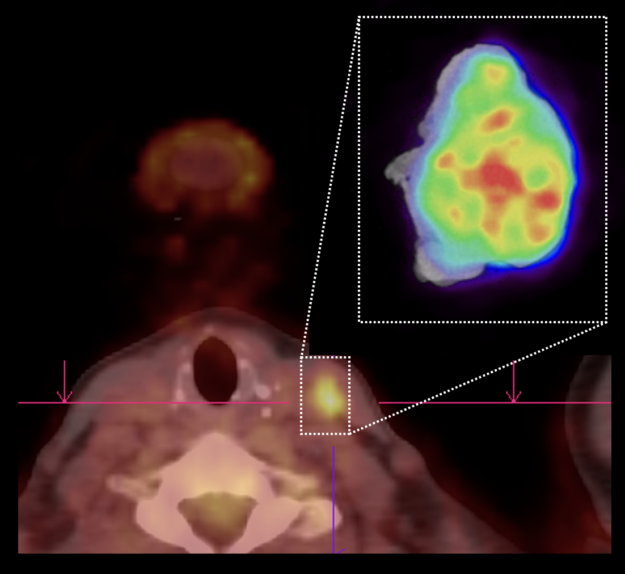

XEOS Aura 10 PET-CT | Case 9: Papillary thyroid Carcinoma

(linkki artikkeliin tekstin jälkeen) XEOS AURA 10 | Case 9: Papillary thyroid carcinoma Lue englanninkielinen potilastapaus ”Papillary thyroid carcinoma” (Case 9): https://www.xeos.care/stories/imaging-case-9-papillary-thyroid-carcinoma Tiivistelmä: Papillaarinen karsinooma on yleisin kilpirauhasen syövistä. Riippuen missä vaiheessa diagnosointi tehdään on hoitomuotona yleensä yhdistelmä kilpirauhasen kokopoistoa, kaulan alueen imusolmukkeiden poistoa sekä radiojodihoitoa. Tässä esillä olevassa tapauksessa osoitetaan, kuinka AURA 10 intraoperatiivinen…